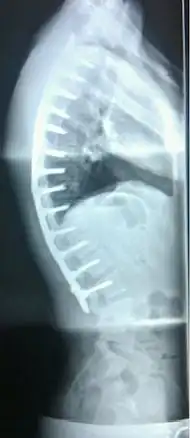

Surgery

In severe or extreme cases, patients may be treated through an extensive surgical procedure in an effort to prevent the disease from worsening or harming the body. The skeletal deformity caused by Scheuermann's disease can be corrected or partially corrected with surgical procedures, almost all of which include multi-level spinal fusion and hardware instrumentation, i.e., rods, pedicle screws, etc. It is important to realize the surgery aims to reduce pain, and not cosmetic defect. As always, surgical intervention should be used as a last resort once conservative treatment fails or the patient's health is in imminent danger as any surgical procedure is not without risk. However, the chances of complication are relatively low, and the surgeries are often successful.

There are two primary surgical techniques to correct kyphosis: posterior-only fusion and anterior/posterior fusion. While debate lingers over which surgical approach is optimal, several studies published since 2018 suggest treatment trends are favoring posterior-only fusion.[17][18][19]

The classic surgical procedure entails entering two titanium rods, each roughly 1.5 feet (0.46 m) long (depending on the size of the kyphosis) into the back on either side of the spine. Eight titanium screws and hardware are drilled through the bone to secure the rods onto either side of the spine. On the internal-facing side of the spine, ligaments (which can be too short, pulling the spine into its abnormal shape) must be surgically cut or released, not only stopping part of the cause of the kyphosis, but also allowing the titanium rods to pull the spine into a more natural position. The damaged discs between the troubled vertebrae (wedged vertebrae) are normally removed and replaced with bone grafting from the hip or other parts of the vertebrae, which once healed or "fused" will solidify. The titanium instrumentation holds everything in place during healing. The patient can expect to remain in hospital for a minimum of a week, and possibly longer. They may then be required to wear a brace for several months more to ensure the spine heals appropriately. The titanium instrumentation may stay in the body permanently, or be removed years later. Patients who have undergone such surgery may need physical therapy to manage pain and mobility. Recovery can be prolonged: typically patients are not allowed to lift anything above 5–10 pounds (2.3–4.5 kg) for 6 months to 1 year, and many are out of work for 3 to 6 months. However, once the fusion is solidified, most patients can return to their usual lifestyle within 1–2 years.

Prognosis

Spinal fusion for kyphosis and scoliosis is an extremely invasive surgery. The risk of complications is estimated to be about 10%. Possible complications may be inflammation of the soft tissue or deep inflammatory processes, breathing impairments, bleeding and nerve injuries, or infection. As early as five years after surgery around 5% require reoperation and long-term issues remain unclear.[20][21]